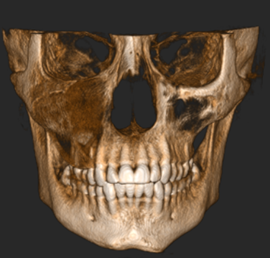

Estudios de imagen

Como estudio imagenológico inicial, se le realizó ortopantomografía, donde se apreció la lesión radiopaca de bordes irregulares y difusos en el cuadrante superior derecho que se extendió en sentido cefálico caudal con ocupación del seno maxilar derecho, y en sentido mesio-distal desde la unidad 1.3 hasta la unidad 1.7. Posteriormente se le indicó una tomografía computarizada cone beam, donde se apreció que el límite superior de la lesión coincide con el borde inferior del cuerpo malar, extendiéndose hasta el pilar cigomático maxilar, tal como se muestra en las Figuras 3, 4 y 5.

Figura 3. Reconstrucción 3D en una vista trans axial de los huesos del macizo cráneo facial y la zona afectada por la lesión. Fuente: Historia Clínica Postgrado Cirugía bucal ULAC-IDOLA Julio 2021

Figura 4. Reconstrucción 3D volumen rendering, en una vista frontal de los huesos de la cara y zona afectada por la lesión. Fuente: Historia Clínica Postgrado Cirugía bucal ULAC-IDOLA Julio 2021

Figura 5. Reconstrucción multiplanar donde se observa la displasia en cortes: axial, sagital y coronal. Fuente: Historia Clínica Postgrado Cirugía bucal ULAC-IDOLA Julio 2021